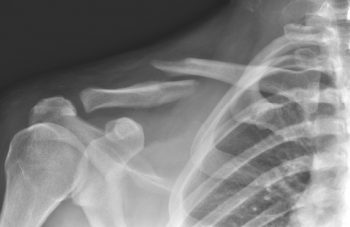

Перелом ключицы со смещением и без симптомы и лечение Автор Екатерина Михайлюк | дата обновления 19.01.2017Мой мирВконтактеОдноклассники Рубрика: Поделись в соцсетяхВконтактеОдноклассники